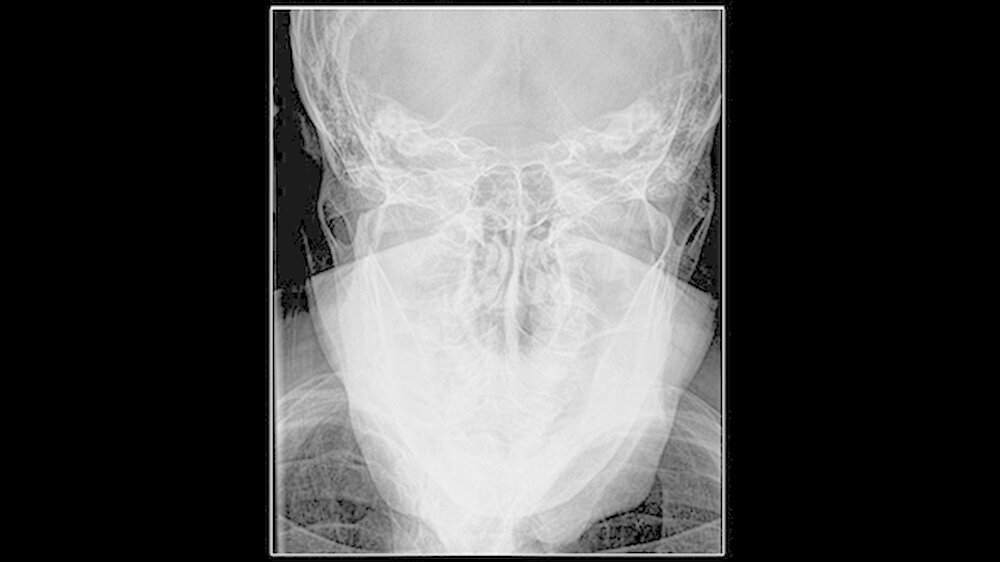

Die klinische Untersuchung zeigte eine überwärmte, schmerzhafte Schwellung präauriculär links und eine stark eingeschränkte Mundöffnung bei zahnlosem Kiefer. Das angefertigte Orthopantomogramm und die Schädelaufnahme in posterior-anteriorer Projektion gaben keinen eindeutigen Hinweis auf Pathologien im Bereich des linken Kiefergelenks, mit denen die ausgeprägten Beschwerden der Patientin hätten erklärt werden können.

Es war lediglich ein stark verschmälerter Gelenkspalt im Bereich des linken Kiefergelenks erkennbar, woraufhin eine Computertomografie des Unterkiefers durchgeführt wurde (Abbildungen 1 und 2). Dabei zeigten sich eine Deformierung des linken Kiefergelenksköpfchens mit Unregelmäßigkeiten der Kortikalis sowie eine Fremdkörpereinlagerung (freie Gelenkkörperchen) im Bereich des Gelenkspalts (Abbildungen 3 und 4).